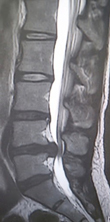

せぼねの変形や椎間板の傷み具合、不安定性の有無、脊柱管の狭さ、またせぼね全体のバランスなどを見るためにX線検査やCT検査、MRI検査などを行います。進行例では脊柱管の狭さをより詳しく評価するために入院して脊髄造影検査や、同時にどの神経が痛みの原因となっているかを明らかにするために神経の枝に直接麻酔薬を注入する選択的神経根ブロックを行う場合があります。成人期では血管性の下肢の痛みがないか評価するために両手足の血圧を測ったり、骨粗鬆症の有無を評価するために骨密度検査を行うこともあります。

椎間板の傷み具合や膨隆の程度、不安定性の有無、またせぼね全体のバランスなどを見るためにX線検査やCT検査、MRI検査などを行います。その他、入院して行う脊髄造影検査や、神経の枝に直接麻酔薬を注入する選択的神経根ブロック、あるいは椎間板造影や椎間板ブロックを行うこともあります。成人期では血管性の下肢の痛みがないか評価するために両手足の血圧を測ったり、骨粗鬆症の有無を評価するために骨密度検査を行うこともあります。

せぼねの変形や椎間板の傷み具合、すべりや不安定性の程度、脊柱管の狭さ、またせぼね全体のバランスなどを見るためにX線検査やCT検査、MRI検査などを行います。進行例では脊柱管の狭さをより詳しく評価するために入院して脊髄造影検査や、同時にどの神経が痛みの原因となっているかを明らかにするために神経の枝に直接麻酔薬を注入する選択的神経根ブロックを行う場合があります。成人期では血管性の下肢の痛みがないか評価するために両手足の血圧を測ったり、骨粗鬆症の有無を評価するために骨密度検査を行うこともあります。

せぼねの変形や椎間板の傷み具合、すべりや不安定性の有無、脊柱管の狭さ、またせぼね全体のバランスなどを見るためにX線検査やCT検査、MRI検査などを行います。進行例では脊柱管の狭さをより詳しく評価するために入院して脊髄造影検査や、同時にどの神経が痛みの原因となっているかを明らかにするために神経の枝に直接麻酔薬を注入する選択的神経根ブロックを行う場合があります。成人期では血管性の下肢の痛みがないか評価するために両手足の血圧を測ったり、骨粗鬆症の有無を評価するために骨密度検査を行うこともあります。